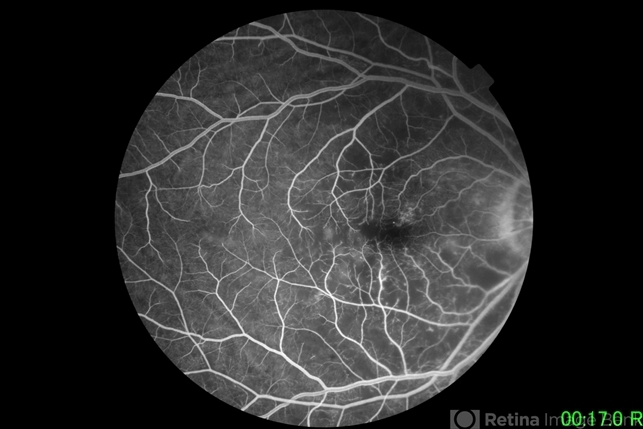

- COVID-19, branch retinal artery occlusion (BRAO)

- 77 year old female who had loss of vision on her right eye 6 hours after her vaccination for COVID-19. The patient has hypertension with poor control, maintained on oral medications on an irregular basis. She has no prior hospitalizations related to COVID-19.